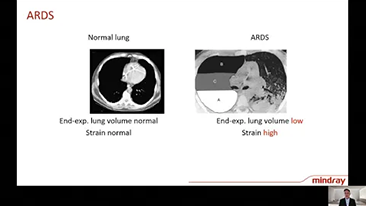

Das Beatmungsger?t im Einzelnen richtig einzustellen, ist bei der Behandlung von Patientinnen und Patienten mit Atemwegserkrankung von entscheidender Bedeutung . Da diese Einstellungen in Bezug auf s?mtliche Parameter von einem Arzt oder einer ?rztin vorgenommen werden, h?ngt ihre Angemessenheit direkt von deren Wissen und der Erfahrung, die sie mit solchen Einstellungen gesammelt haben, ab. In den letzten 20 Jahren hat sich der in der BeatmungsunterstĂŒtzung verfolgte Ansatz grundlegend weiterentwickelt. Ausgehend von den BedĂŒrfnissen der Praxis wurden zahlreiche Beatmungsmodi und Tools zur EntscheidungsunterstĂŒtzung entwickelt, die Zeit einzusparen und Fehler zu vermeiden helfen.